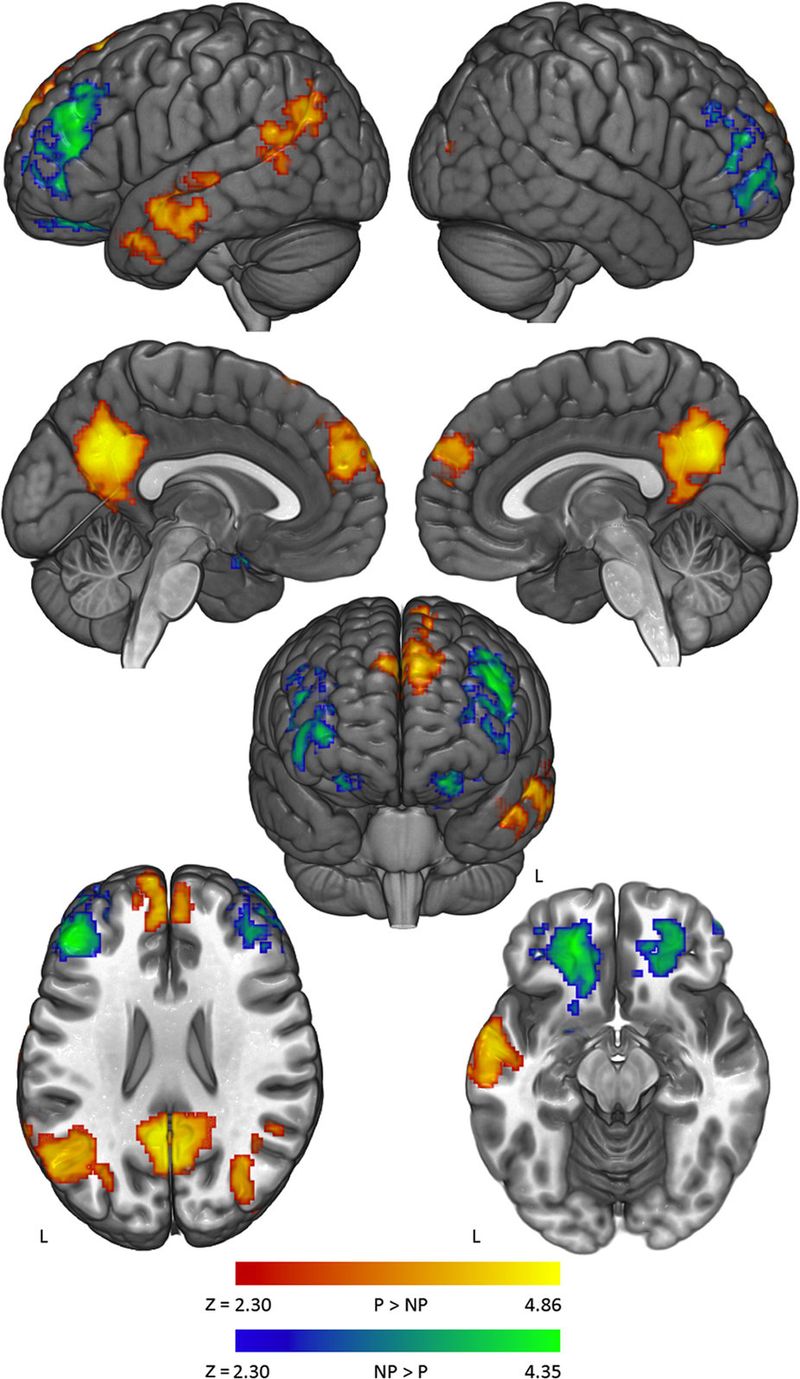

There was. Notably, Kaplan and colleagues saw increased activation with the political arguments in what’s called the “default mode network.” That’s a collection of brain structures implicated “in mind wandering, in memory, in thinking about yourself and your identity,” Kaplan says. The study also found increased activation in the amygdala, a region of the brain that correlates with negative emotions.

Basically, the results suggest the participants are engaging the same regions of the brain where we contemplate our identities and feel threats. And it’s presumably within these circuits that the roadblocks to accepting facts lie.

Recently, Kaplan has found more evidence that we tend to take political attacks personally. In a study recently published in Scientific Reports, he and collaborators took 40 self-avowed liberals who reported having “deep convictions,” put them inside in a functional MRI scanner, and started challenging their beliefs. Then they watched which parts of the participants’ brains lit up. Their conclusion: When the participants were challenged on their strongly held beliefs, there was more activation in the parts of the brain that are thought to correspond with self-identity and negative emotions.